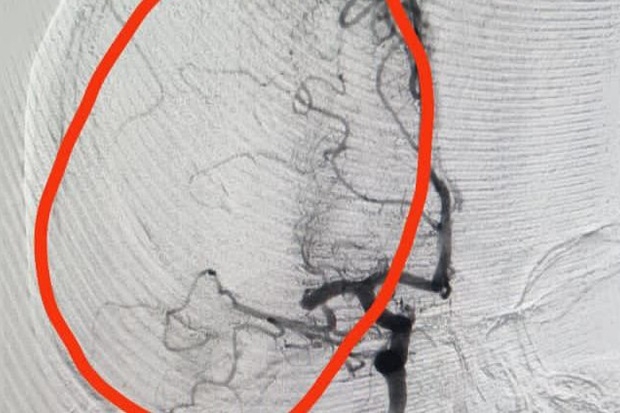

Как сообщили журналистам телеканала «Волгоград1» в пресс-службе комитета здравоохранения Волгоградской области, волгоградские врачи спасли 43-летнюю женщину от инсульта, проведя операцию по удалению тромба из головы. Жительница Санкт-Петербурга приехала в Волгоград погостить к родственникам, утром у нее ухудшилось самочувствие. В больнице женщине провели КТ и КТ-ангиографии и обнаружили причину. Сейчас пациентке лучше, ей требуется дальнейшее лечение.